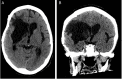

Figure 1

Figure 1. Axial (A) and coronal (B) CT of the head showing right-sided basal ganglia intraparenchymal hemorrhage measuring 8.5 × 4.3 × 3.8 cm with associated brain compression, midline shift, intraventricular extension, and mild perilesional edema.